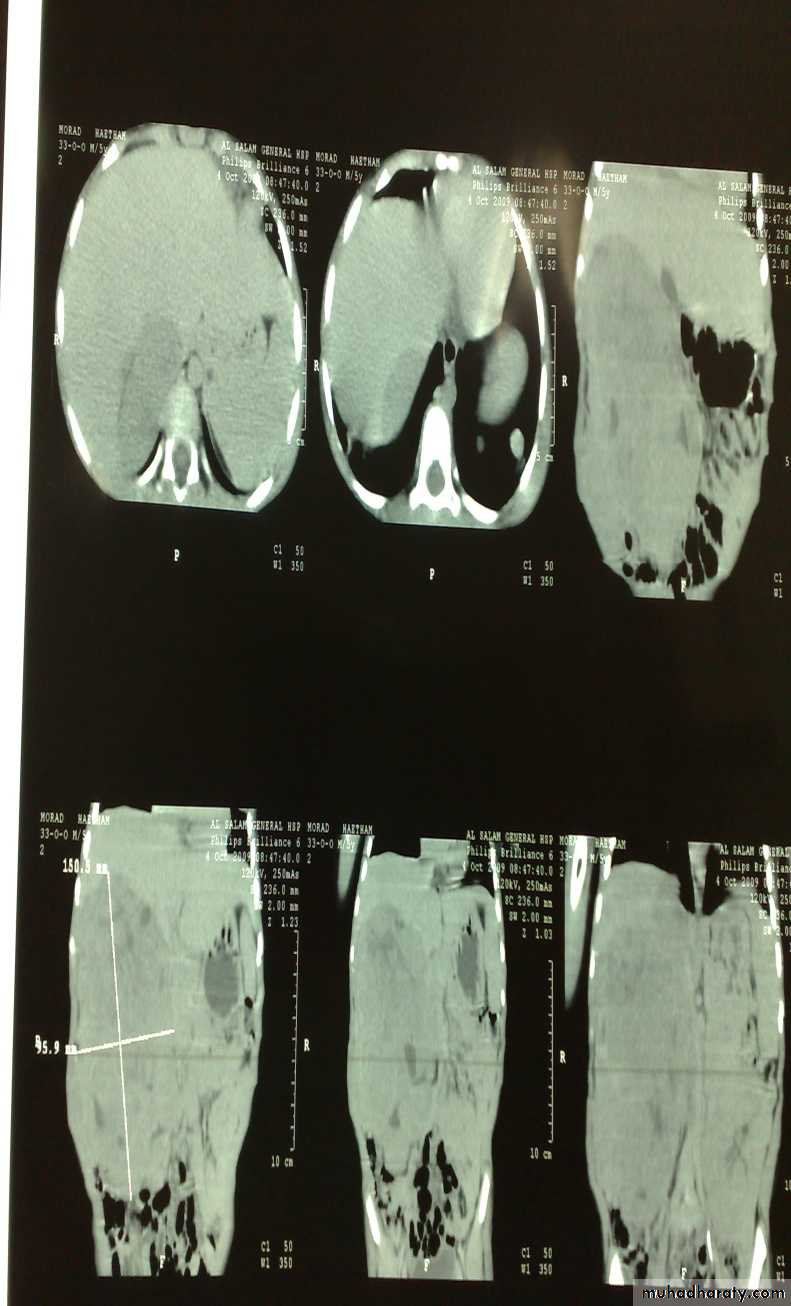

The Child with an Abdominal Mass5 years child, presented with mass in the flank.

DDx of mass in the flank:1- Wilms tumor

2- Neuroblastoma

3- Neglected PUJ obstruction

Presentation:

1- Mass2- hematuria

3- hypertension

Treatment by surgery remove the kidney + chemotherapy

Neuroblastoma in the adrenal gland